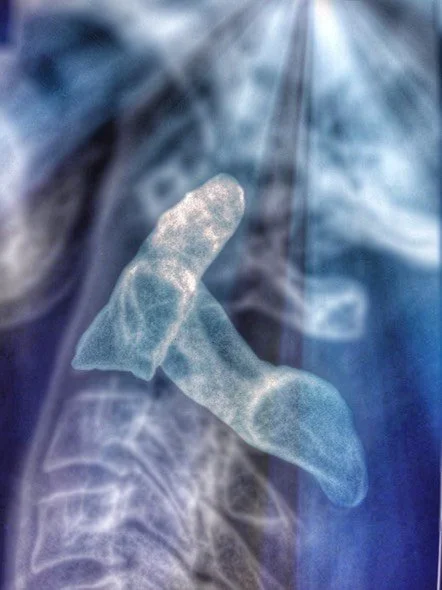

Avant toute action, il y a une analyse/appréciation. Chez nous les Chiropraticiens ça s’appelle faire une Anamnèse (on pose des questions) et un Examen (on inspecte, ausculte, teste). On arrive à un Diagnostique (on pose un nom à une certaine symptomatologie). Pour mieux discerner un problème, on va procéder à faire des radios/résonances magnétiques/scanners, une analyse de sang ou d’urine. Le Chiropraticien est autorisé à faire ces examens. En cas de doute, on envoye le patient à un autre spécialiste pour une clarification de la situation (Radiologue, Neurologue, Orthopédiste, Urologue,…). Finalement on arrive au Traitement.

-Le docteur Lindsay J. Rowe D.C., M.D., DACBR: Un géant dans la radiologie dans l’enseignement comme dans la publication des livres de radiologie. Ses cours de radiologie sont d’une finesse remarquable: le compliqué rendu simple. Un grand merci pour ses enseignements éclairer aux US au NWCC et plus tard dans des diffèrent séminaires.